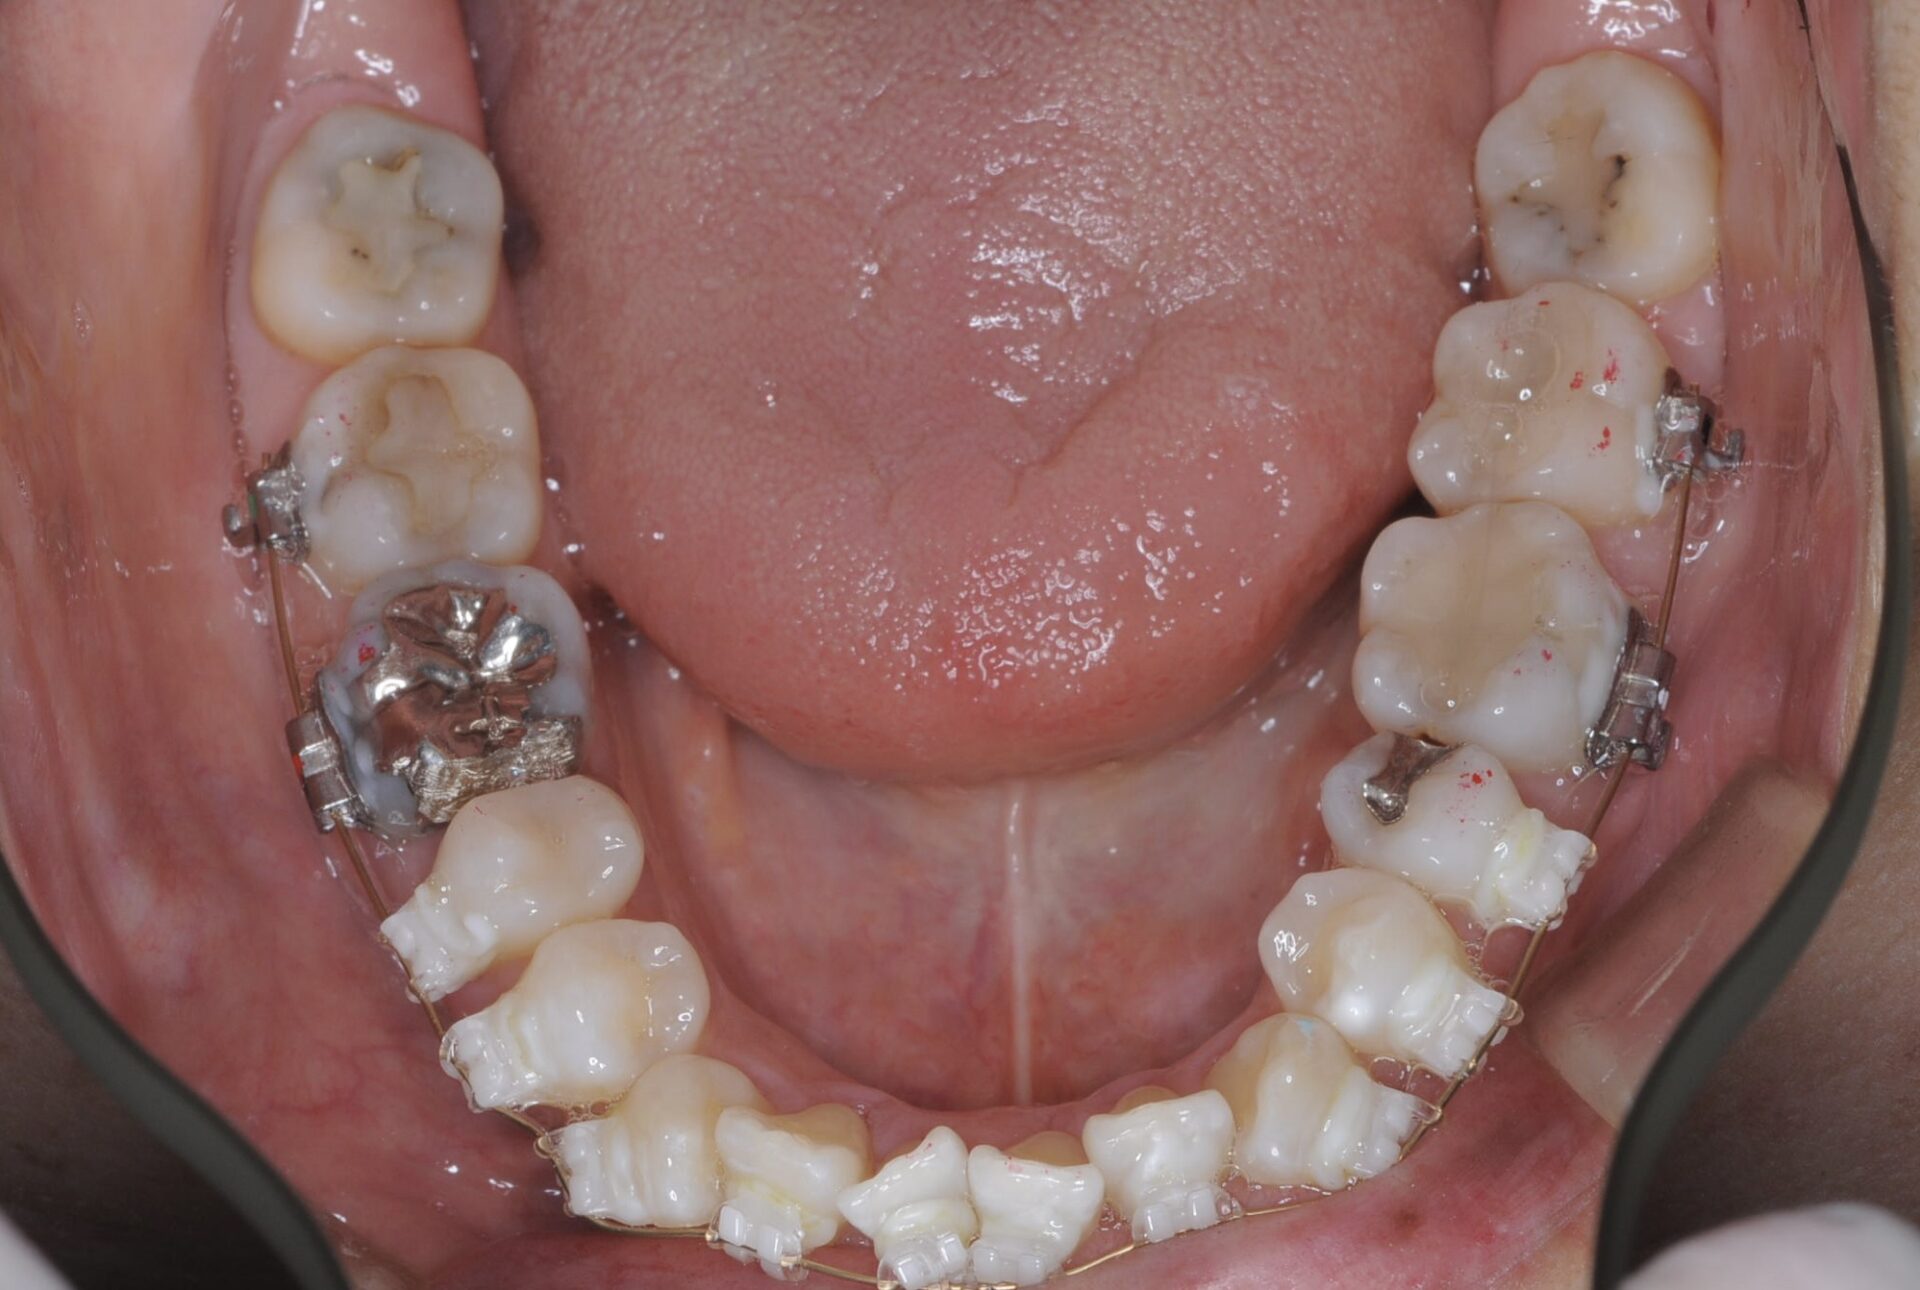

矯正治療スタート時(下顎)

メインテナンス時(下顎)